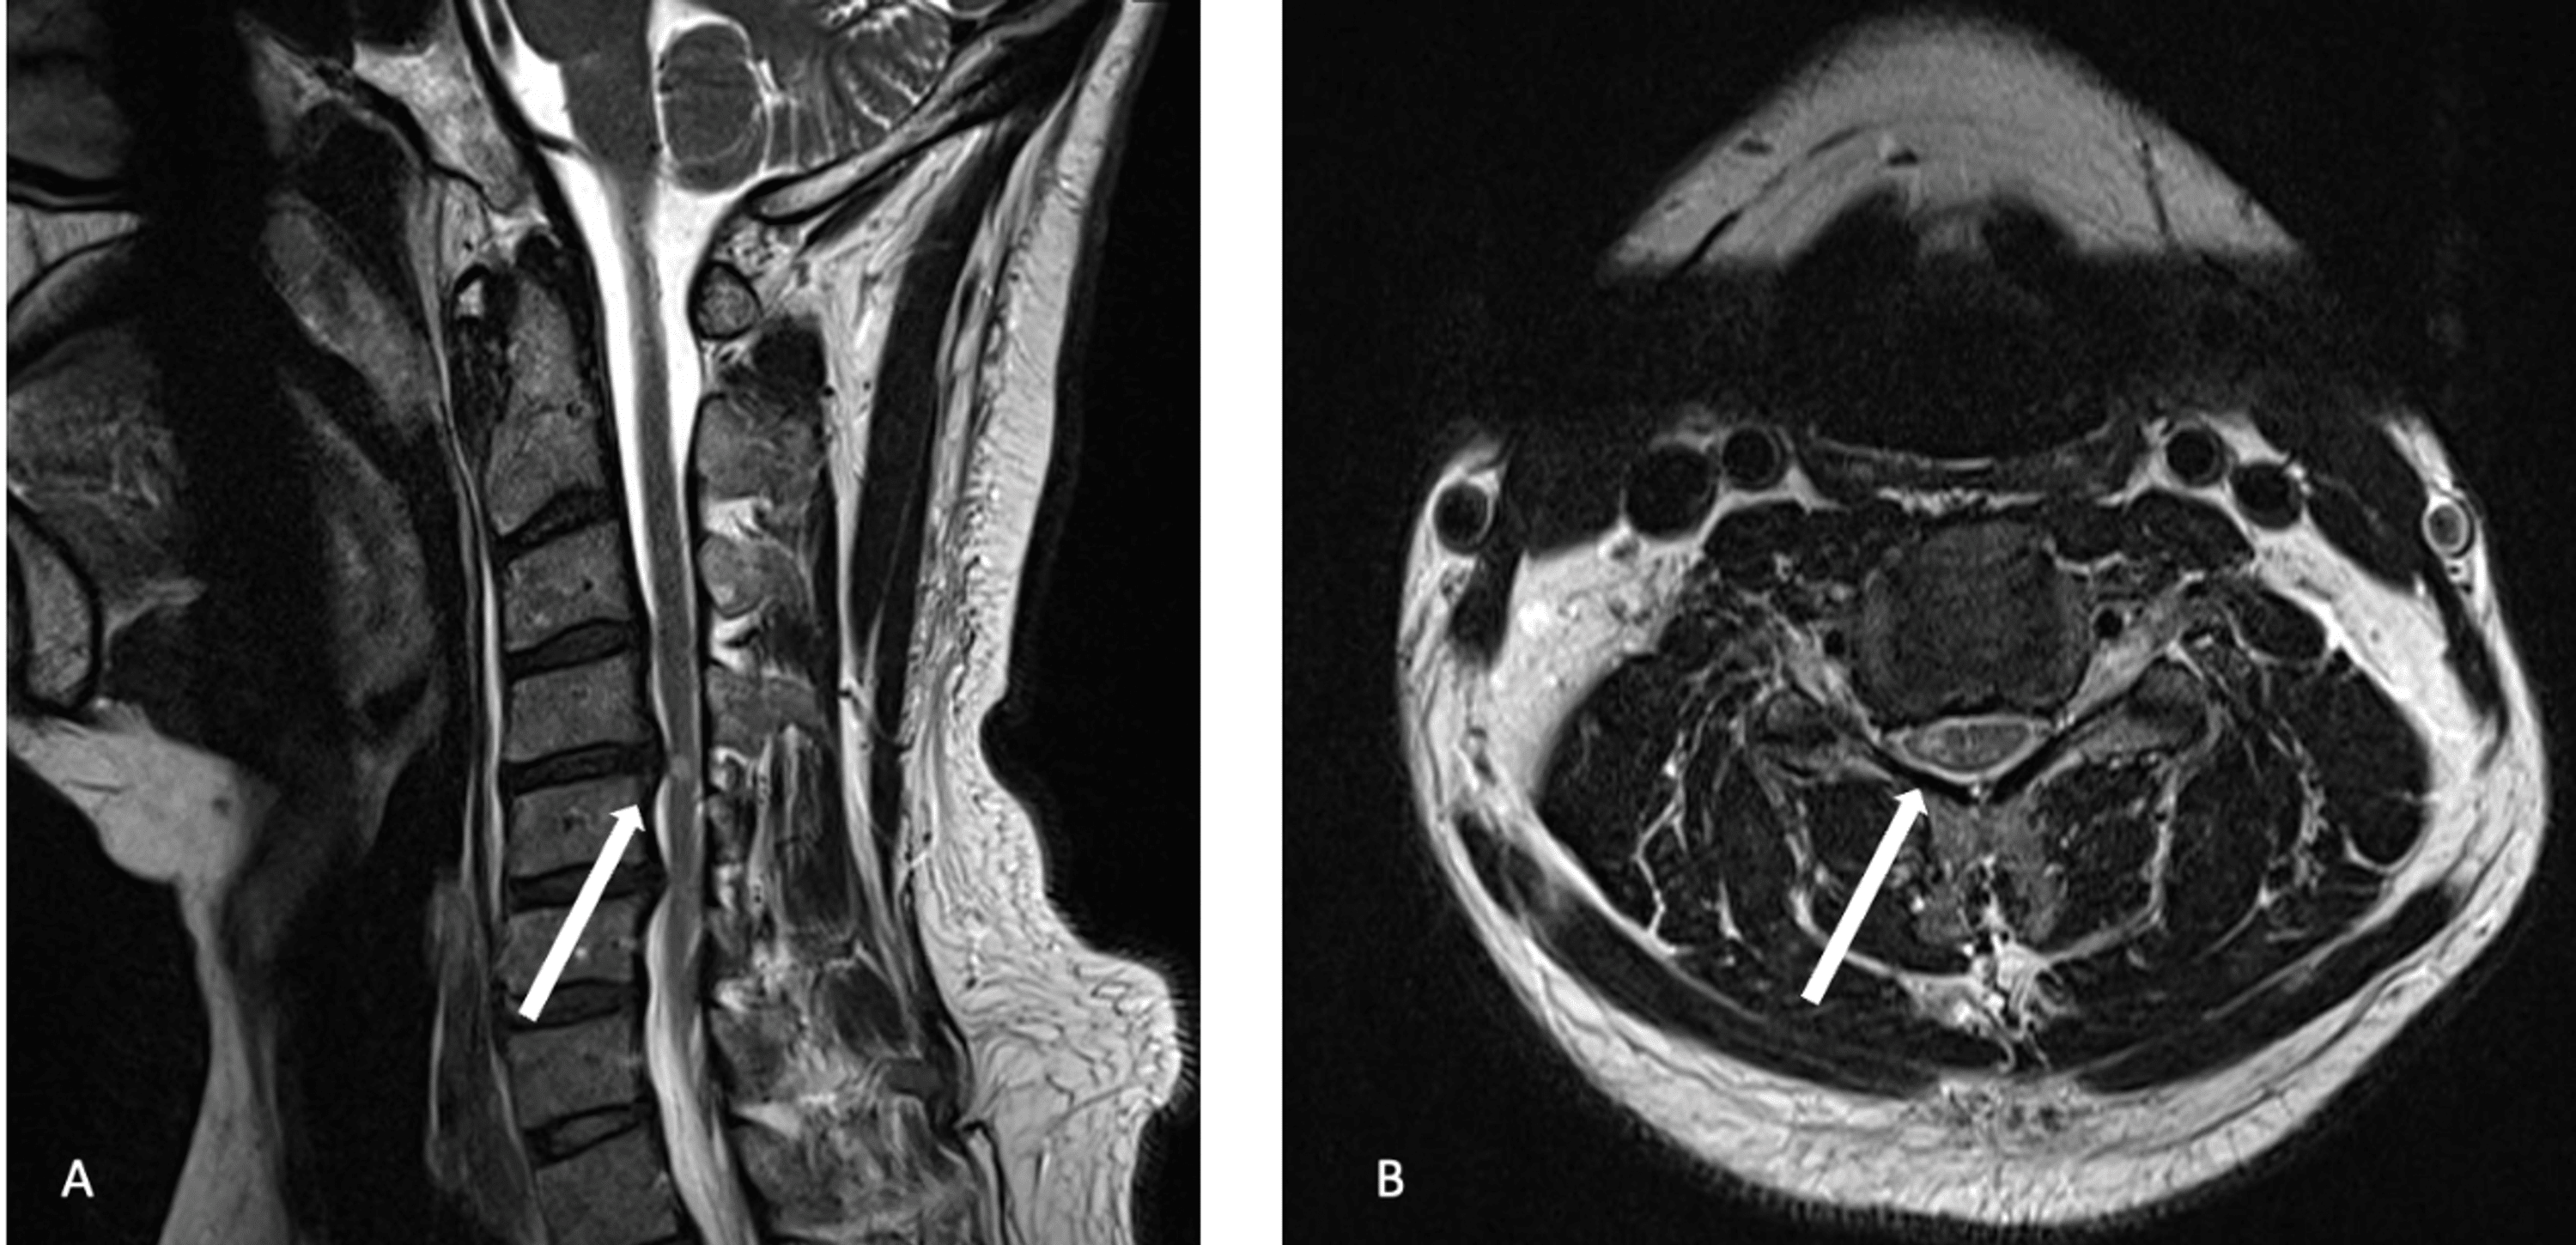

Figure 3 from Utility of Flexion and Extension MRI for Evaluating Isolated Cervical Spinal Cord

Utility of Flexion and Extension MRI for Evaluating Isolated Cervical Spinal Cord Lesions A Flexion Extension C Spine Mri What is a cervical spine mri? The potential importance of flexion/extension mri in the elucidation of cervical cord compression. Also, in only 15 of 52 patients identified with pc3 (21%) could the cord. Dynamic mri will show the flexional and extensional position of cervical spine other than neutral position. There are important differences between a normal vs abnormal cervical mri. Flexion Extension C Spine Mri.

Utility of Flexion and Extension MRI for Evaluating Isolated Cervical Spinal Cord Lesions A Flexion Extension C Spine Mri Dynamic mri will show the flexional and extensional position of cervical spine other than neutral position. What is a cervical spine mri? The potential importance of flexion/extension mri in the elucidation of cervical cord compression. Mri stands for m agnetic. Also, in only 15 of 52 patients identified with pc3 (21%) could the cord. There are important differences between a. Flexion Extension C Spine Mri.

Figure 3 from Utility of Flexion and Extension MRI for Evaluating Isolated Cervical Spinal Cord Flexion Extension C Spine Mri There are important differences between a normal vs abnormal cervical mri which which will be discussed below. Dynamic mri will show the flexional and extensional position of cervical spine other than neutral position. Mri stands for m agnetic. Also, in only 15 of 52 patients identified with pc3 (21%) could the cord. What is a cervical spine mri? The potential. Flexion Extension C Spine Mri.

Figure 3 from Utility of Flexion and Extension MRI for Evaluating Isolated Cervical Spinal Cord Flexion Extension C Spine Mri Dynamic mri will show the flexional and extensional position of cervical spine other than neutral position. What is a cervical spine mri? There are important differences between a normal vs abnormal cervical mri which which will be discussed below. Also, in only 15 of 52 patients identified with pc3 (21%) could the cord. The potential importance of flexion/extension mri in. Flexion Extension C Spine Mri.

Figure 3 from Utility of Flexion and Extension MRI for Evaluating Isolated Cervical Spinal Cord Flexion Extension C Spine Mri Also, in only 15 of 52 patients identified with pc3 (21%) could the cord. What is a cervical spine mri? There are important differences between a normal vs abnormal cervical mri which which will be discussed below. Mri stands for m agnetic. Dynamic mri will show the flexional and extensional position of cervical spine other than neutral position. The potential. Flexion Extension C Spine Mri.